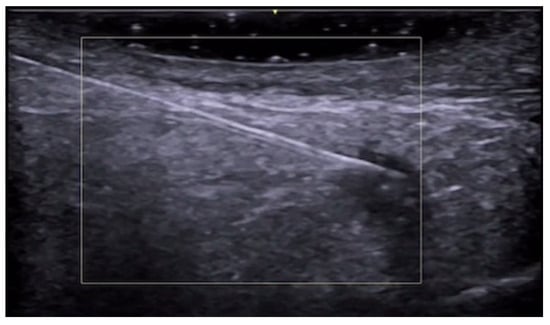

- Iannone, M.; Janowska, A.; Oranges, T.; Balderi, L.; Benincasa, B.B.; Vitali, S.; Tonini, G.; Morganti, R.; Romanelli, M.; Dini, V. Ultrasound-guided injection of intralesional steroids in acute hidradenitis suppurativa lesions: A prospective study. Dermatol. Ther. 2021, 34, e15068. [Google Scholar] [CrossRef] [PubMed]

- Sechi, A.; Patrizi, A.; Raone, B. Intralesional steroid injections to target sinus tract fibrosis in hidradenitis suppurativa: Results from an ultrasound-based retrospective study. Dermatol. Ther. 2022, 35, e15710. [Google Scholar] [CrossRef]